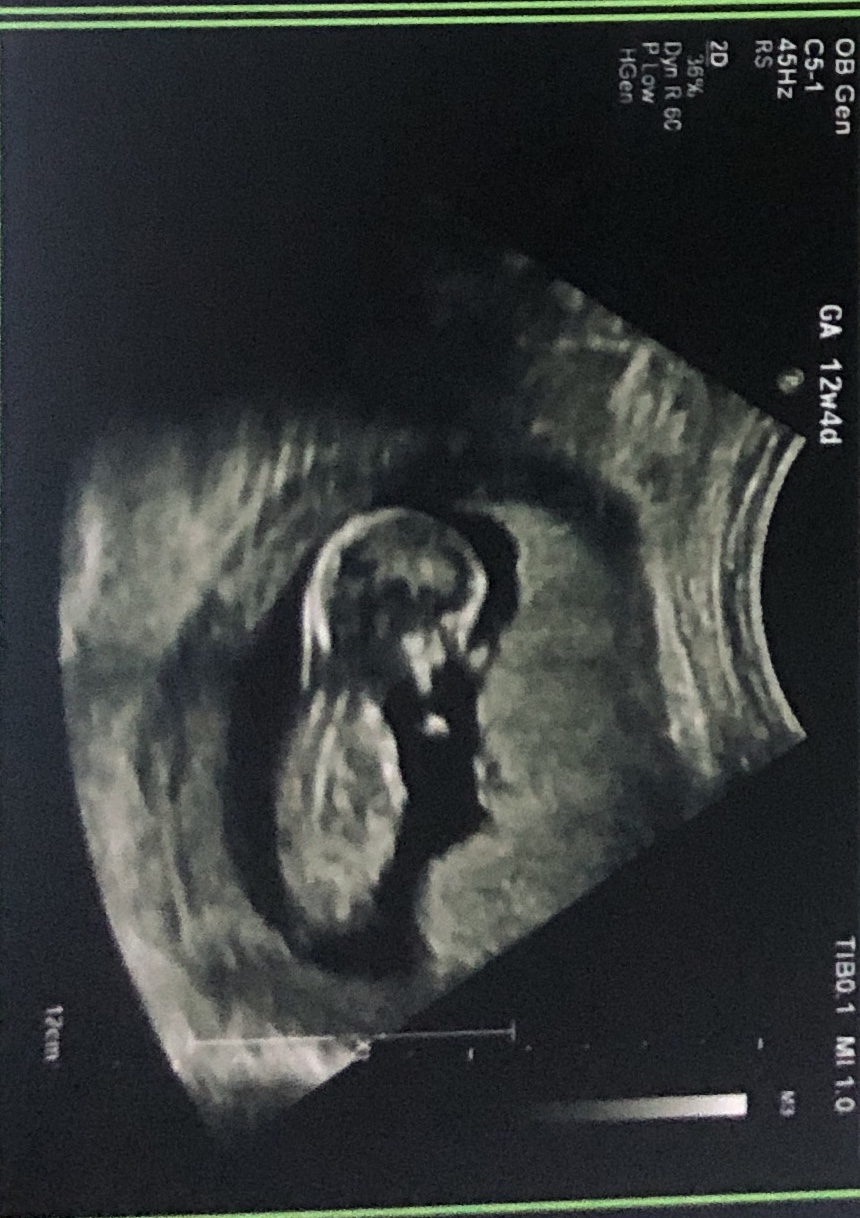

Im on my mobile atm and my pic is rubbish but I think little ones leg is hiding all the clues! Do you have any more pics or video maybe just incase :)

Cant see a nub to guess on, sorry

It's a bit early for me and I think the baby is turned away from the camera just a bit, and the end of the nub is cut off - I would hesitate to guess on these but would be happy to guess on any more pics you have in a week or two.

Baby is still keeping secrets! Sonja do you have any video you can add to youtube and post for us?